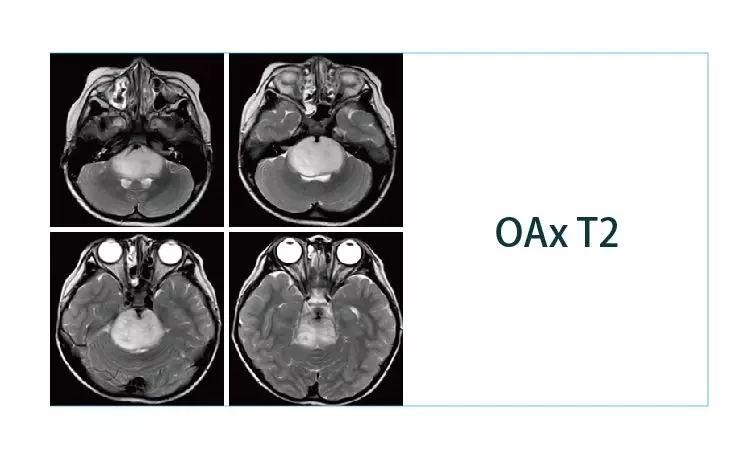

【朗润影像档案】20190329磁共振影像病例结果讨论

【朗润影像档案】磁共振影像病例分享(编号20190329)